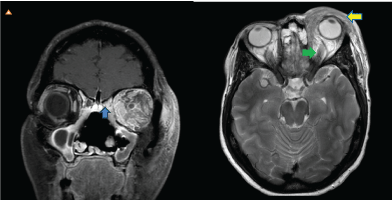

A 50-year-old lady presented with a one month history of progressively enlarging, painful left orbital swelling. She had failed outpatient oral antibiotic therapy. Physical examination was significant for left periorbital and orbital swelling, proptosis, mechanical ptosis, tenderness, edema, erythema and warmth. Visual acuity was 20/20 with restriction of extraocular movements. Laboratory workup showed normal white cell count, erythrocyte sedimentation rate, elevated C reactive protein and positive wound culture growing rare leukocytes and Staphylococcus aureus. Magnetic resonance imaging of the orbits and face showed left orbital cellulitis with subperiosteal enhancement, erosive changes in the ethmoid air cells and lateral displacement of left globe (Figure 1). She was started on broad spectrum antibiotics on which she failed to improve. Diagnostic left caruncular orbitectomy with biopsy was done which showed dense lymphoplasmacytic infiltrate, fibrosis and many eosinophils (Figure 2 and Figure 3). Immunohistochemical studies revealed diffusely positive > 100 IgG4 cells/HPF (Figure 4). This was diagnostic for IgG4 related disease [1]. Serum IgG4 level was only mildly elevated at 129 mg/dL. She was started on intravenous methylprednisolone 60 mg with dramatic improvement in symptoms and was discharged on prednisone.

Figure 1: MRI coronal T1 post contrast with fat saturation showing left sided subperiosteal enhancement and erosion of the adjacent ethmoid air cells [blue arrow]. Axial enhanced fat suppressed T2 MRI showing preseptal [yellow arrow] and postseptal enhancing tissue with lateral displacement of globe [green arrow].